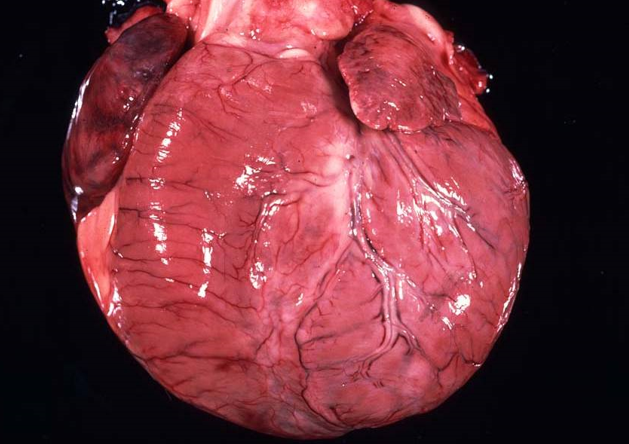

How does Hypertrophic cardiomyopathy present grossly?

Hearts are enlarged (increased cardiac silhouette)

Prominent concentric hypertrophy of the left ventricle, interventricular septum

Dilation of the left atrium